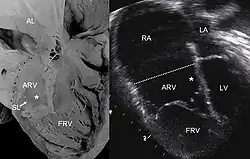

Anomalia Ebsteina (ang. Ebstein's anomaly) – wrodzona, przewodozależna, sinicza wada serca, która dotyczy zastawki trójdzielnej. Jeden lub dwa płatki tej zastawki przemieszczone są w kierunku koniuszka do jamy prawej komory. Płatek przedni łączy się z prawidłowo położoną częścią dysplastycznego pierścienia, przegrodowy odchodzi od przegrody, a tylny od okolicy koniuszka. Zastawka nie jest prawidłowo wykształcona, co objawia się mniejszą, lub większą jej niedomykalnością[1].

Przemieszczone płatki dzielą komorę prawą na dwie części:

- proksymalną, tylną, zatrializowaną,

- dystalną, przednią właściwą, odgrywającą rolę pompy wyrzucającej krew do płuc.